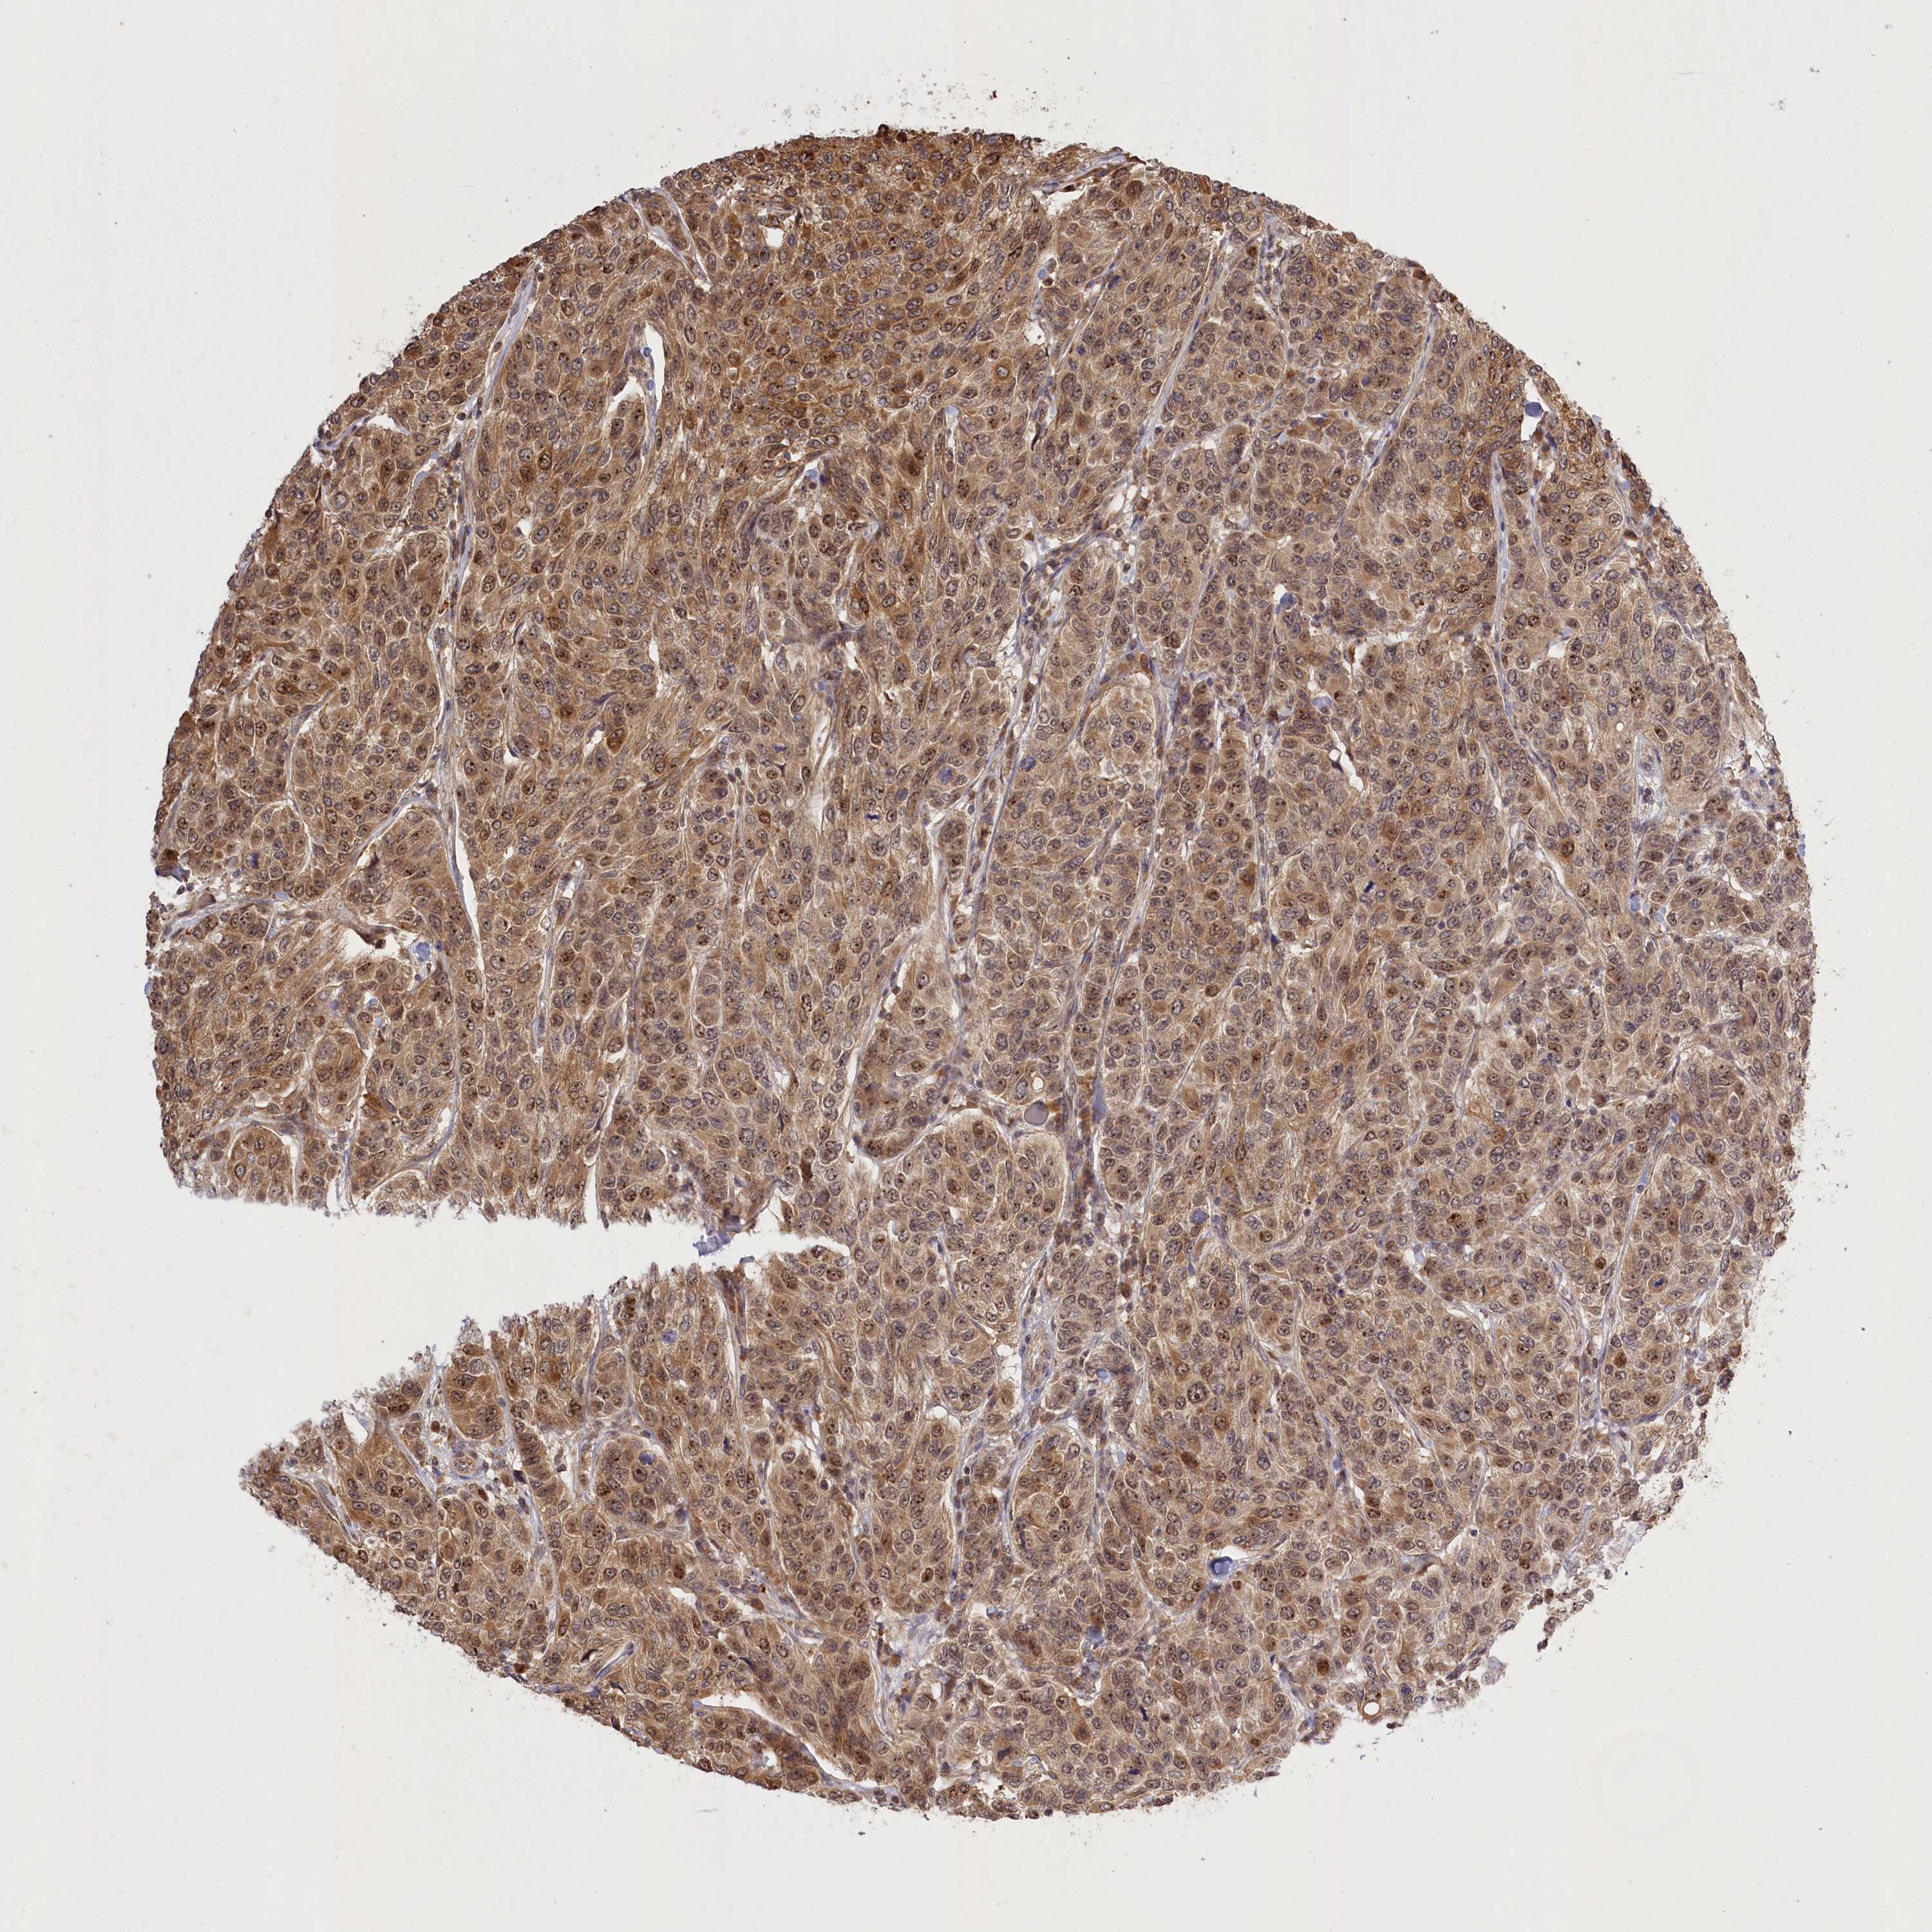

CANCER BREAST CANCER Show tissue menu

BRCA TCGA BRCA VALIDATION PROTEIN EXPRESSION